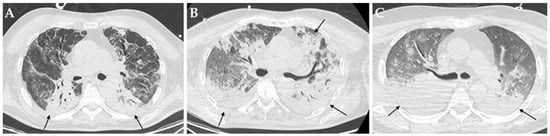

Figure 2.

Axial HRCT images of different patients (A–C) with COVID-19 ARDS admitted to ICU showing bilateral consolidations (black arrows). In particular, all these patients developed a pulmonary superinfection by Klebsiella pneumoniae (A), Pseudomonas aeruginosa plus Acinetobacter baumannii (B) and Staphylococcus aureus plus Candida albicans.